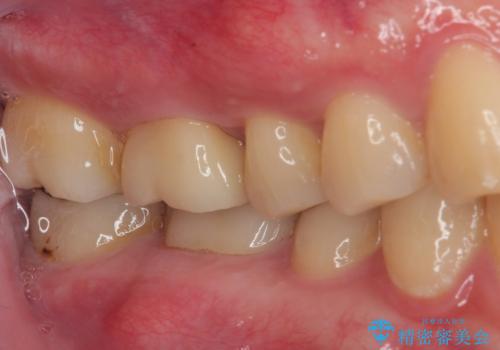

痛みもなく、適合もよく、機能的に問題もなく、見た目も満足されていました。

嚙む力(咬合力)がとても強い方なのでナイトガードを今後使っていただく予定です。